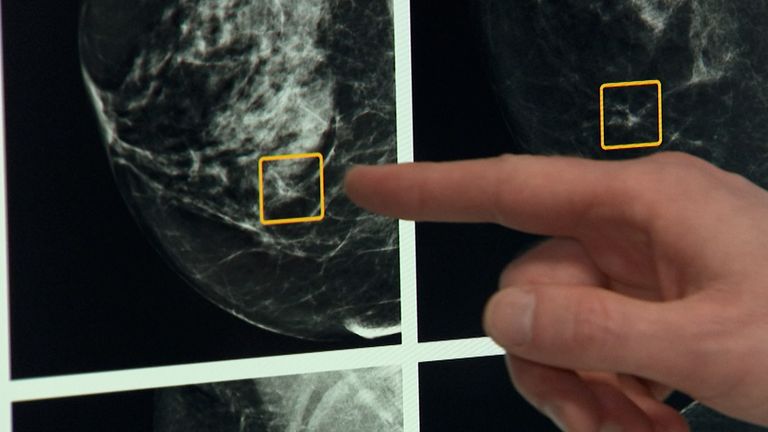

A new three-drug combination could help women with a common form of aggressive breast cancer live longer, a study has suggested.

Researchers used a blood test known as a liquid biopsy, which detects tumour DNA in the blood, to test for the PIK3CA mutation.